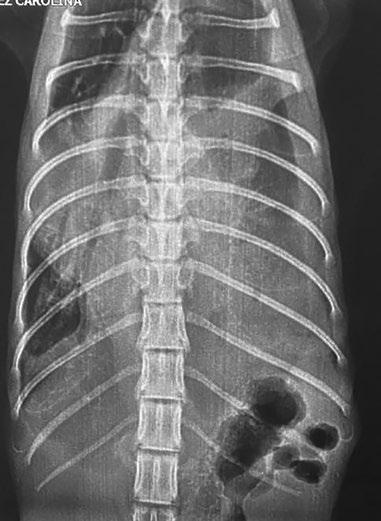

Los traumatismos en los gatos son frecuentes. A pesar de una buena supervivencia general hasta el alta, es una de las principales causas de muerte1,2. En el registro de traumatismos del ACVECC-VetCOT, la caída desde una altura, el atropello por un vehículo y la causa desconocida de la lesión (es decir, el gato aparece lesionado después de haber desaparecido) son las tres principales causas de lesiones contundentes en los gatos, mientras que la herida por mordedura y la lesión penetrante desconocida encabezan la lista de causas penetrantes (datos no publicados, registro del VetCOT de 2017-2019). Las cinco principales causas de mortalidad en gatos (que reflejan lesiones complejas) son el atropello, la expulsión de un vehículo, la herida por mordedura no penetrante (lesión por aplastamiento), la lesión balística y la lesión por asfixia/tracción. Los factores que influyen en el resultado incluyen el grado de la lesión y los recursos disponibles (médicos y económicos) para identificar y tratar las lesiones3. Por estas razones, se recomienda un abordaje sistemático de lo que puede ser una situación compleja y dinámica4,5. Una evaluación primaria completada rápidamente, seguida de una evaluación secundaria, permiten identificar las lesiones, determinar las intervenciones y evaluar si los cuidados definitivos pueden lograrse con los recursos locales frente a la necesidad de derivar a un hospital veterinario con recursos adicionales (p. ej., productos sanguíneos, técnicas de imagen avanzadas, atención especializada).

En el informe del registro del VetCOT de 2013-2017 de más de 3.400 gatos con lesiones traumáticas, el 16,5 % tenía evidencia de lesión craneal.

En el informe del registro del VetCOT (Veterinary Committee on Trauma Registry Report) de 2013-2017 de más de 3.400 gatos con lesiones traumáticas, el 16,5 % tenía evidencia de lesión craneal y el 8,7 % de traumatismo de la columna vertebral2. Durante la evaluación primaria se ha de determinar la puntuación de la escala de coma de Glasgow modificada para evaluar la lesión cerebral, y deben realizarse y determinarse la palpación